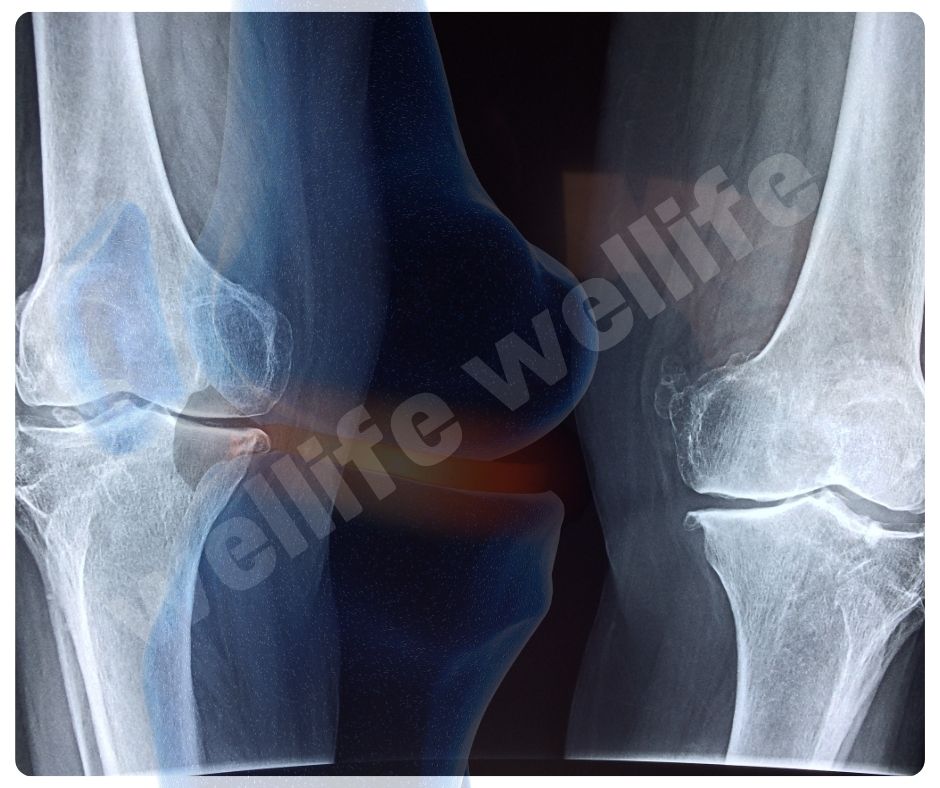

콘드로이친 효능 중 가장 대표적인 것은 골관절염(Osteoarthritis) 완화입니다. 골관절염은 연골이 닳아 없어지면서 통증과 강직을 유발하는 만성 질환인데요, 콘드로이친은 연골 손상을 줄이고 증상을 완화하는 데 효과적이에요.

- 연골 보호 및 재생: 콘드로이친은 연골의 구조를 유지하고, 손상된 연골의 재생을 돕는 효능이 있습니다.

- 통증 완화: 관절 통증을 줄이고, 관절의 기능을 개선하는 데 도움을 줍니다.